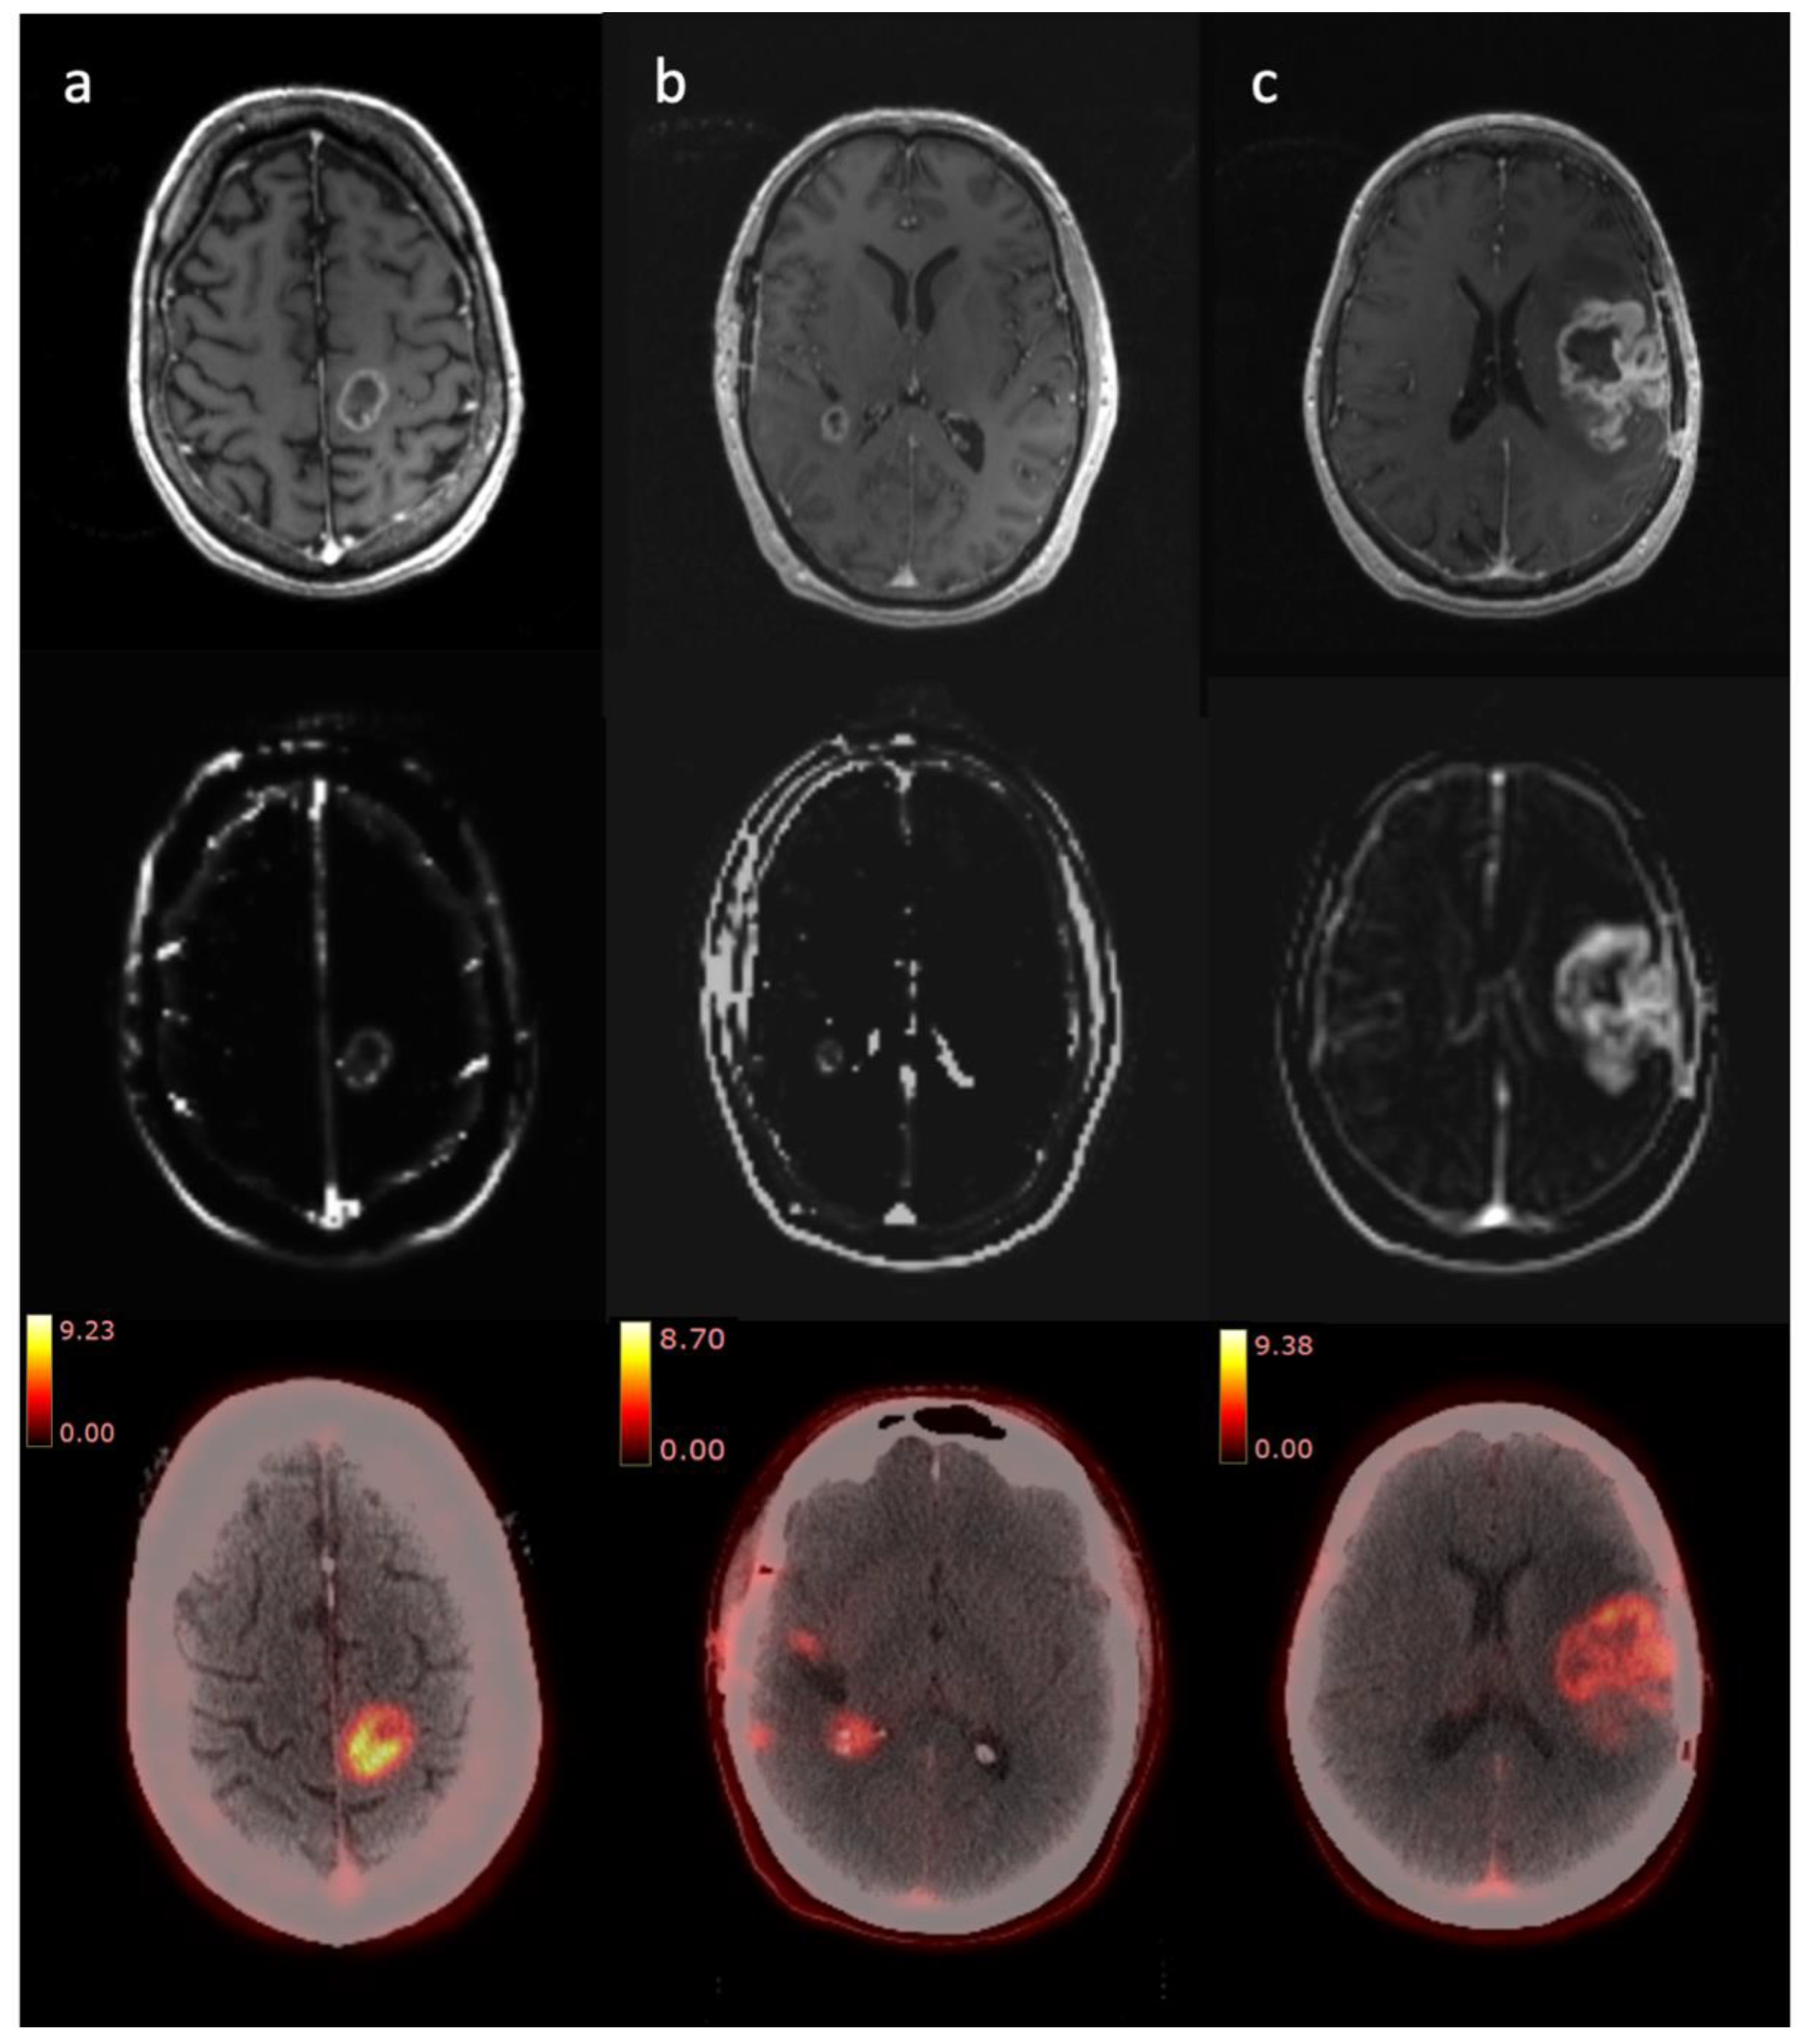

3.2. Clinical Imaging

3.2.1. Radiologist Assessment

3.2.2. Tumour Volume Analysis

Short Survival

Long Survival